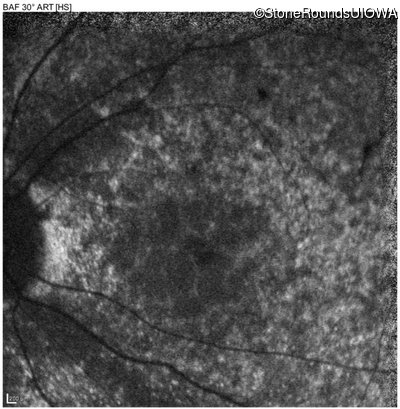

Age at visit: 13 years

Age at visit: 14 years

Diagnosis & molecular findings

Disease Gene Allele 1 variant(s) Allele 2 variant(s) Inheritance mode

AR Stargardt Disease ABCA4 IVS38-10T>C IVS38-10T>C AR